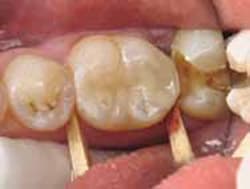

Because the preparation was more than 3 mm deep, a thin layer of resin-modified glass ionomer light-cure liner (Ionoseal, VOCO, https://www.voco.com) was used to protect the pulp. The enamel cavosurface margin was etched with phosphoric acid for 15 seconds and thoroughly washed with air and water. After air drying without desiccating, a self-etch bonding system (iBond®, Heraeus Kulzer) was used for the preparation according to the manufacturer’s instructions. The first layer of bonding agent was placed and agitated for 20 seconds, followed by good air drying for 5 seconds, then light-cured (Figure 3).